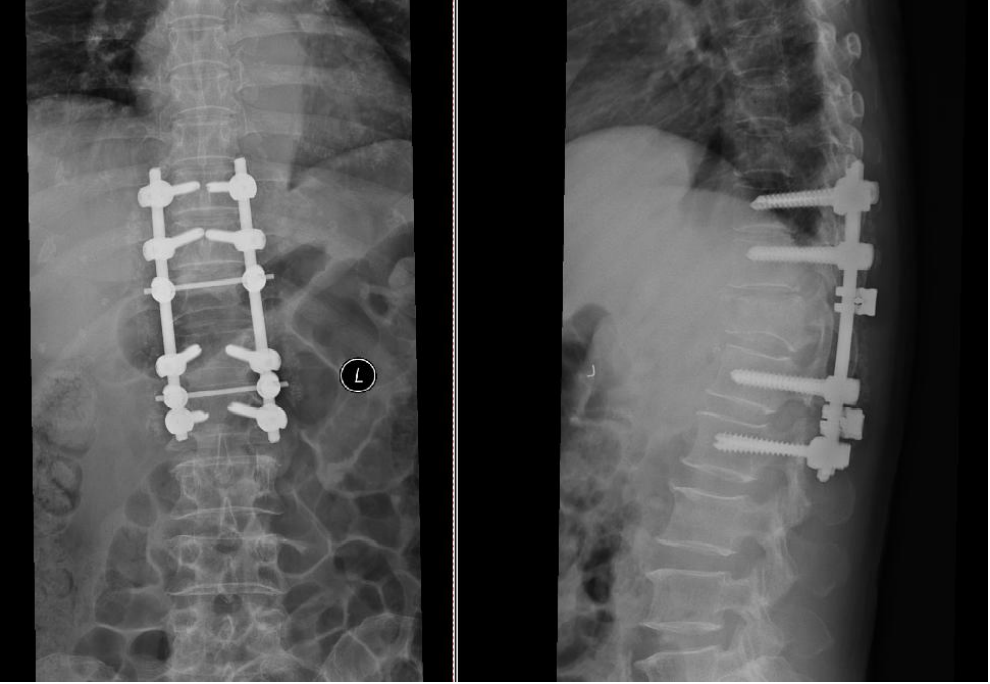

病例2车祸伤,完全性脊髓损伤

AO分型

- 分型:T12L1 C型;T12 B2型,L1 A1型

- 神经功能障碍分级:N4

- 修正参数:

- AO补充评分:C+N3(8+4) 12分

TLICS评分

- 骨折脱位(3分)

- 完全性神经损伤 (2分)

- PLC断裂(3分)

- 8分

载荷评分

- 碎裂大于60% 3分

- 后凸4~9度 2分

- 移位大于50% 3分

- 8分,合并脱位

治疗方案:手术治疗;后路手术,长节段固定